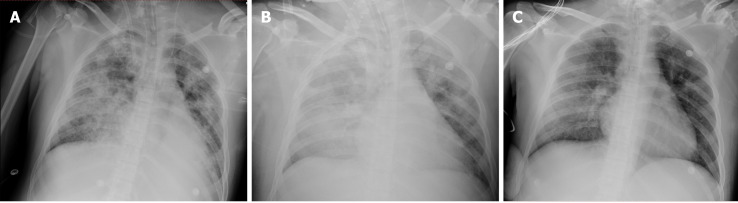

Figure 1.

Changes in chest computed tomography. A: The chest computed tomography (CT) on admission showed mild pulmonary contusion on both sides of the lung; B: The chest CT after intubation and support of extracorporeal membrane oxygenation (ECMO) revealed substantial consolidation in both lungs; C: The chest CT on the second day after the termination of ECMO showed resolution of the lung consolidation.

The patient experienced multiple traumas when his motorcycle collided with a truck. On admission to our emergency department, he was conscious and had a slight cough and a small amount of bloody sputum. His blood pressure and breathing were stable, with an oxygen saturation (SpO2) of 95%-97% at 5 L/min of mask O2. Whole-body computed tomography (CT) showed a left fifth rib fracture and mild PC (Figure 1A) as well as fractures to the left clavicle and scapula, pubis, left femoral shaft and right ulna. After plaster fixation of his right upper arm, he was admitted 18 h after the onset of mild PC to the orthopaedic ward for further surgical treatment. There he received an analgesic, antibiotics and left tibial tuberosity traction treatment. However, he developed severe chest tightness, chest pain, dizziness and haemoptysis 19 h later. Clinical examination revealed severe hypoxia with an SpO2 of 68%, tachypnoea (respiratory rate: 36 breaths/min) and tachycardia (heart rate: 157 bpm). Endotracheal intubation was subsequently performed, and a large amount of bloody sputum was suctioned from the endotracheal tube. The patient was transferred to the intensive care unit (ICU) 15 min later.

Bedside chest X-ray showed diffuse infiltration on both sides (Figure 2A). After ECMO was established, chest CT and pulmonary artery imaging were performed, at which point there was no evidence of a pulmonary embolism, but substantial consolidation was noted in both lungs (Figure 1B). Fibreoptic bronchoscopy revealed diffuse and profuse blood in all bronchopulmonary segments and fresh bleeding was observed in the trachea and right bronchus.

On day 13, fibreoptic bronchoscopy revealed blood clots on the bronchial wall but no active bleeding. Bedside chest X-ray showed significantly decreased lung infiltration (Figure 2C); thus, ECMO support was terminated on day 13. On the second day after ECMO termination (day 15), we performed another chest CT scan, which revealed further dissipation of lung consolidation (Figure 1C). Tracheostomy was performed on day 15, and the patient was weaned from the ventilator on day 21. He then returned to the orthopaedic ward and underwent surgery for his left clavicle, left femur and right ulna. The patient was discharged 1 wk later. The changes in PC and the course of treatment are presented in Table 1.